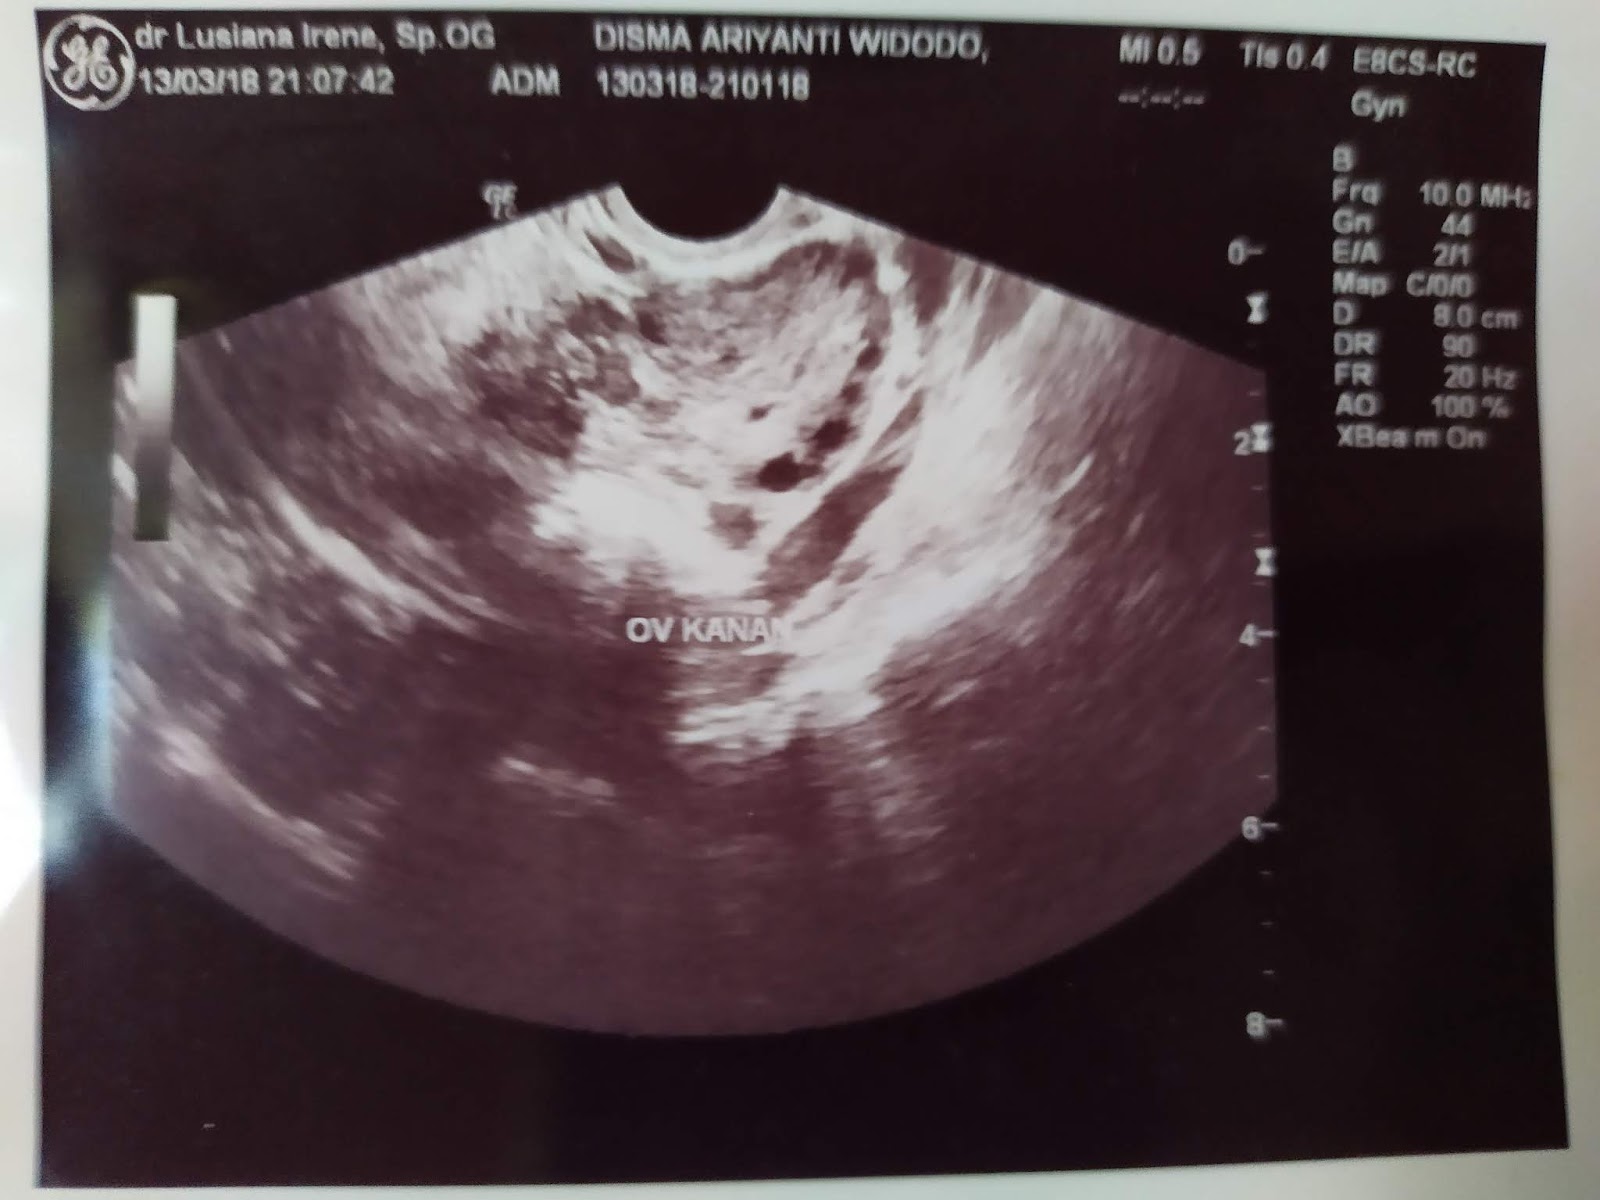

Gambar Usg Sel Telur Matang

BEGINI GAMBAR SEL TELUR YANG SUBUR… - dr Yudhistya SpOG | Facebook Story of My Journey: TTC Journey #2 USG Folikel dan Hasil Analisa Sperma Aku dan PCOS (Hasil USG Trans Vaginal) - JalanSenja.com Cerita Promil 4 - Polycystic ovary (PCO) - Fika Putri Cerita Promil 2 - USG Transvaginal dan Tes Sperma - Fika Putri Semua Akan Terjawab di Waktu yang Tepat - kumparan.com Promil Story : MIMPI BURUK ITU BERNAMA PCOs - The Arsalan Family Journal Penting Dilakukan Wanita, Ketahui Sel Telur Dalam Tubuhmu Jangan Sampai “Mandul” Karena Kehabisan Program Hamil di Dokter Lusiana Irene, SpOG Jogja Manusia sedikit tahu..sel telur kecil tidak mungkin hamil | Dr Suryo, SpOG - Kesehatan Reproduksi C e r i t a C i k i: Sel Telur Kecil-Kecil EFEK PENYUBUR Pada wanita normalnya sel… - dr Yudhistya SpOG | Facebook Ikhtiar yang ke dua – Part 2 (H6-H11) – Bread and Butter Letter Promil Step 4 – Baby Journey PCOS adalah… | Kisah Ibuknda (pakai ‘k’) :D Room | ‘Aisyah Tsurayya Inart’s Story - Yah, Saya Akhirnya Hamil - I’m 1 In 10: My PCOS Story Kisah Perjuangan Terbaru Tya Ariestya Saat Jalani Program IVF | Popmama.com story of my lyfe: pejuang keturunan Nikita Mirzani Bagikan Hasil USG Bayi Kembar, Dapatkah Gen Kembar Diturunkan? - Semua Halaman - Intisari lihat hasil USG tranvaginalku wktu bulan Januari 2013 apa itu PCO? - IbuHamil.com Cerita Promil 4 - Polycystic ovary (PCO) - Fika Putri aq PCO bund, ada yg bisa bantu baca hasil USG intravagina q??? - IbuHamil.com Hasil USG Sel Telur Yang Subur - YouTube Pengalaman Bayi Tabung/ IVF (Part II) Update with Pict! | honeymenulis’s Blog Inart’s Story - Yah, Saya Akhirnya Hamil - Story of My Journey: June 2017 Ingin Terhindar dari Kista? Jauhi 4 Jenis Makanan Enak Ini Sekarang! - Semua Halaman - Grid Health Program Hamil Bulan ke-1 : PCOS Survivor | Lanalouie Embrio 3 cm berapa minggu. minggu: bayi Anda sebesar tongkol jagung BEGINI GAMBAR RAHIM YANG SUBUR… - dr Yudhistya SpOG | Facebook PCOS | medicalstudentnotes USG Transvaginal: Penjelasan, Prosedur & Manfaat (Lengkap) | Friso BILIK SONOGRAFER : Kista Ovarium Kontrol H+10 (Cek Perkembangan Sel Telur) Istilah kehamilan dipertimbangkan dengan USG. Kehamilan kebidanan dan embrio Selamat Pagi Senin Ayah Bunda. Semoga… - Dokterkandungan. id | Facebook My First USG | Story of Us Menuju Hamil – Part 2 of 3 – Edward Suhadi Apa itu PCOS? Kenapa Sulit Hamil? | Sunshine of My Life Setiap Ibu Hamil Harus Tahu, Kapan Harus Melakukan USG lewat Vagina? - Semua Halaman - Nakita Program Hamil di Dokter Lusiana Irene, SpOG Jogja Saat Sel Telur Berukuran Kecil dan Sulit Dibuahi - Health Liputan6.com Kabar Gembira, Ini Tanda Awal Sel Telur Berhasil Dibuahi oleh Sperma | Popmama.com 101+ Gambar Cek Sel Telur Paling Hist - Gambar Pixabay Kontrol H+12 (Mendebarkan, apakah sel telurnya tetap berkembang?) Program Kehamilan Balasan dari Saya Penderita PCOS, Saya Berhasil Hamil | KASKUS Pembekuan Sel Telur: Fungsi, Prosedur, dan Komplikasi INGIN HAMIL – Siklus Ovarium dan Tanda-Gejala Wanita Subur | JuliantoWitjaksono.com 6 Fakta Mengejutkan Tentang Sel Telur Wanita - YouTube Pengalaman Hamil Kembar - The Urban Mama Maimuns — PCOS? Deal with it! Berapa Sisa Sel Telur di Tubuh? Bisa Dicari Tahu | Parenting.Dream.co.id PCOS Polycystic Ovary Syndrom Apakah… - Komunitas Impian Bunda | Facebook Persiapan Hamil (4) – jurnal Ammi Wanita Hasilkan 2 Sel Telur dalam Masa Ovulasi, Bisakah Terjadi? Promil Story : MIMPI BURUK ITU BERNAMA PCOs - The Arsalan Family Journal My journey to motherhood: HSG, Tes Sperma, hingga PCO Polikistik Ovarium (PCOS): Haid sering tidak datang, Berkumis, Berjerawat, Ingin hamil sulit | Dr Suryo, SpOG - Kesehatan Reproduksi PCOS dan Metformin. Sohib karib! – Cerita Bumi Blighted Ovum | ~cahaya kebaikan~ Cerita Pengalaman Kehamilan Pertama dan Persiapan Melahirkan Anak Pertama - For The Love of Foods and Beauty Masih banyak yg belum tau.. INSEMINASI… - Bayi Tabung PMC Pekanbaru Cerita Program Hamil dengan Dokter Enny Sp.OG di Yogyakarta ~ Land of Jenganten Semua Akan Terjawab di Waktu yang Tepat - kumparan.com Fika Putri Berbagi Tips: Cara Mengetahui Masa Subur Wanita Berdasar Penghitungan serta Ciri-Cirinya - Garda Remaja GAGAL OVULASI?? SERING TERJADI PADA… - Konsultasi Promil Cepat Hamil dan Alami | Facebook Yosevina Issabela prosespersalinan Instagram posts (photos and videos) - Picuki.com Apa sebetulnya bayi tabung dan bagaimana proses menjalaninya? – Bayi Tabung Penang Di minggu kebidanan mana embrio terlihat. Minggu berapa embrio terlihat pada USG? Apakah prosedurnya aman pada tahap pembentukan anak PCOS itu Variable dan Sangat Rumit Prosedur Bayi Tabung: Sebelum dan Sesudah Mengikutinya - Smarter Health Mengenal Kehamilan Kosong atau Blighted Ovum (BO) - Kompasiana.com Cerita Promil, Perjalanan menuju kehamilan (long story short, I finally got pregnant) - Nyonyah Intan Sindrom Ovarium Polikistik (PCOS) 4D Gallery | Dr Suryo, SpOG - Kesehatan Reproduksi Kapan USG direncanakan selama kehamilan. Apakah saya perlu mempersiapkan prosedur? Keadaan organ reproduksi wanita Irish Bella Hamil Anak Kembar, Sang Ibunda Tak Sangka Bakal Punya 2 Cucu - Halaman all - Tribun Batam Lapsus Kista Ovarii - Apriamalia - [PDF Document] Success story – GLADIOOL IVF RS Indosehat Solo, Jl Solo Sragen Km 11, Kebakramat, Karangdawa (2020) Saya Penderita PCOS, Saya Berhasil Hamil | KASKUS September 2014 - Pipit Widya Aku dan PCOS (Hasil USG Trans Vaginal) - JalanSenja.com Pengalaman PCOS-ku yang Berhasil Hamil Alami - kumparan.com Apakah USG mempengaruhi kehamilan. Bagaimana ultrasound mempengaruhi embrio? Ultrasonografi dilakukan hanya atas kesaksian dokter atau mungkin atas permintaan ibu BAB III - [DOCX Document] Kista Ovarium. - ppt download Biaya USG 3 & 4 Dimensi di Karawang - Perawatan Kesehatan Cerita Pengalaman Kehamilan Pertama dan Persiapan Melahirkan Anak Pertama - For The Love of Foods and Beauty Wanita Punya 400 Sel Telur Setiap Menstruasi, Kenapa Susah Hamil? - Semua Halaman - Nakita Tragis Si Ibu Hamil Dibunuh, Bayi di Dalam Kandungan Dicuri - Halaman all - Warta Kota Perlukah USG Transvaginal saat Program Hamil? | Popmama.com 13 Tanda - tanda Kehamilan Awal yang Bisa Dipercayai - Mamapapa.id Melahirkan bayi kembar pada minggu-minggu kehamilan. Dapatkah dokter tidak melihat bayi kembar dengan USG: diagnosis dini kehamilan ganda PROSES DAN BIAYA INSEMINASI 1. USG USG… - dr Yudhistya SpOG | Facebook